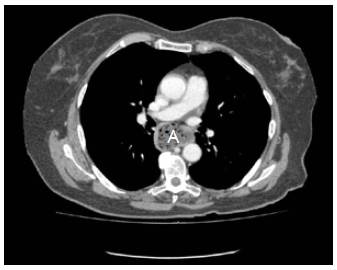

Mujer de 72 años de edad, con cuadro clínico de un año de disfagia y atragantamiento con alimentos sólidos, que había requerido tratamiento endoscópico. Se realiza endoscopia de vías digestivas altas que documenta un divertículo esofágico en tercio medio, y manometría esofágica de alta resolución, sin trastorno motor. El esofagograma (figura 1) y la tomografía computarizada de tórax (figura 2) muestran un divertículo en tercio medio de esófago, lateral derecho, de 7 cm de diámetro y base de 2.5 cm de diámetro. De manera programada se lleva a cabo diverticulectomía esofágica por toracoscopia, en decúbito prono (figura 3), sin complicaciones.